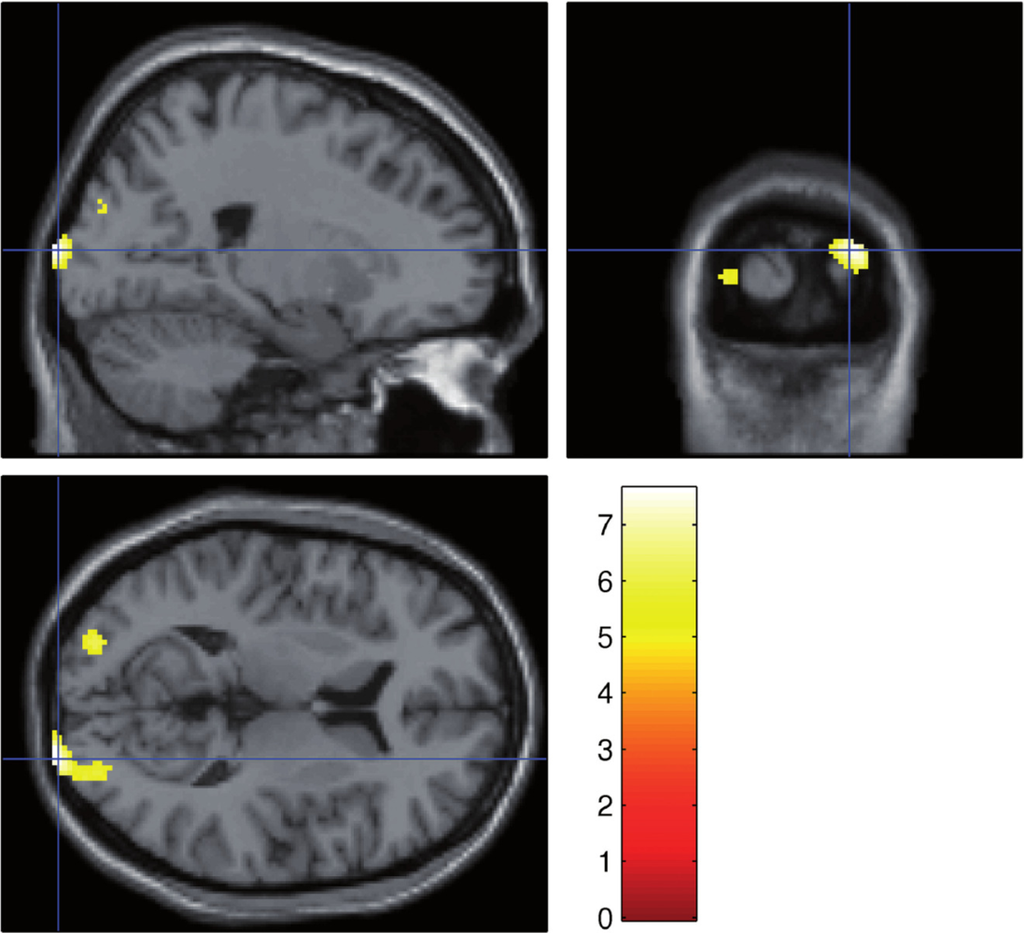

2.2. Functional MRI

- Robinson, S.; Basso, G.; Soldati, N.; Sailer, U.; Jovicich, J.; Bruzzone, L.; Kryspin-Exner, I.; Bauer, H.; Moser, E. A resting state network in the motor control circuit of the basal ganglia. BMC Neurosci 2009, 10, 137. [Google Scholar]